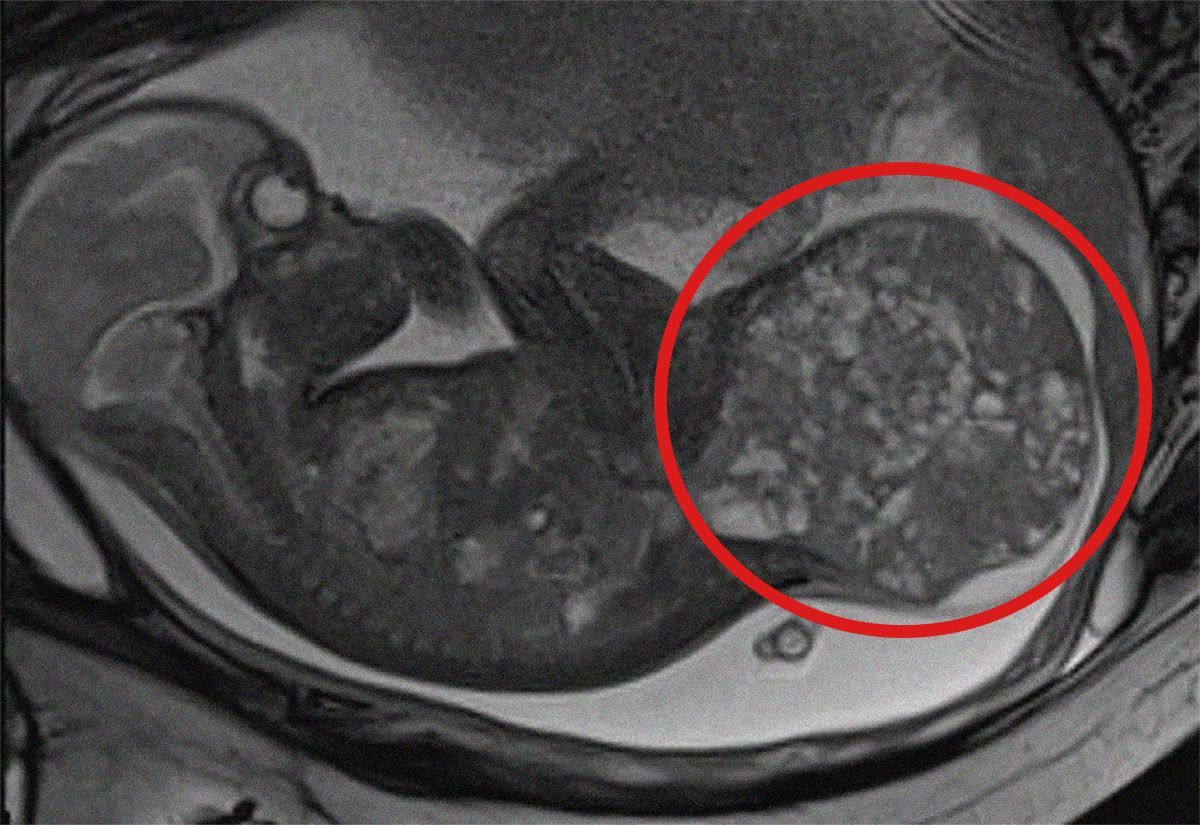

Il tumore era quasi pari alla metà del suo peso alla nascita, una rara neoplasia che colpisce un bimbo ogni 40mila nati vivi e può creare, tra l’altro, gravi problemi cardiaci. Ma la piccola ora sta bene grazie a due interventi chirurgici, uno intrauterino, uno alla nascita. Il giorno del parto la piccola, infatti, pesava 2 kg e il suo tumore 800 grammi. Grazie a un intervento intrauterino salvavita, effettuato mentre era ancora nella pancia della mamma e, subito dopo il parto, a un’operazione chirurgica di rimozione della massa, oggi la piccola – nata prematura alla 30° settimana di gestazione – è in buone condizioni di salute e sta per tornare a casa con la famiglia.

Alla 28° settimana di gestazione, a seguito di una rapida e improvvisa crescita della massa tumorale, gli specialisti dei due ospedali hanno deciso di intervenire in epoca fetale con una procedura mininvasiva di lasercoagulazione ecoguidata dei vasi sanguigni della massa stessa, eseguita presso il comparto operatorio del San Pietro Fatebenefratelli. Utilizzando un laser a diodi è stato così possibile ridurre l’afflusso sanguigno al tumore, rallentandone la crescita e permettendo di prolungare la gravidanza fino alla 30° settimana.

Poi la donna è stata seguita all’ospedale pediatrico Bambino Gesù, dove la mamma ha poi partorito con cesareo programmato nell’ambito del “Progetto Nascita dedicato ai nascituri affetti da gravi patologie congenite. Dopo essere venuta alla luce, la neonata - che prima dell’intervento pesava 1,9 chili - è stata immediatamente operata per rimuovere completamente il teratoma di circa 800 grammi, pari ad oltre la metà del suo peso corporeo effettivo (1,1 kg). L’operazione, della durata di circa tre ore, ha incluso anche la ricostruzione della regione sacrale.